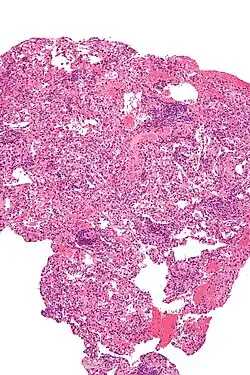

![]() Ilustración que muestra el proceso de un trasplante de pulmón. En la figura A, se cortan las vías respiratorias y los vasos sanguíneos entre el pulmón derecho enfermo y el corazón del receptor. La imagen insertada muestra la ubicación de los pulmones y el corazón en el cuerpo. En la figura B, se cose un pulmón sano de un donante a los vasos sanguíneos y las vías respiratorias del receptor. | ||